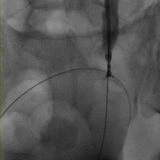

Posizionamento di Stent Nefro-Vescicale

In alcuni casi, viene posizionato uno stent nefro-vescicale quando il drenaggio esterno non è più necessario o desiderato dal paziente. Questo stent può essere posizionato anche in urgenza, ad esempio in presenza di infezioni gravi, insufficienza renale acuta o in pazienti con un solo rene. La sostituzione periodica degli stent può essere eseguita endoscopicamente dall’urologo o sotto guida radiologica dal radiologo interventista, con una procedura rapida e a basso rischio in regime di day surgery.

Quando è presente una stenosi su cicatrice che rischia di occludere l’uretere, si possono utilizzare stent metallici removibili. Questi stent vengono posizionati per mantenere il lume dell’uretere aperto e prevenire l’ostruzione causata dalla cicatrizzazione, e vengono rimossi successivamente sempre sotto guida radiologica.